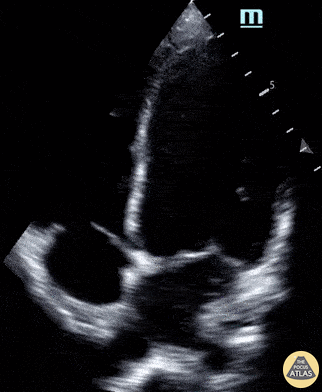

14 year-old male presents to the ED with chest pain two weeks after being having been diagnosed with COVID-19. Labs were notable for elevated CBC, CRP, ESR, and troponin. POCUS revealed moderately decreased function and LV dilation, consistent with the diagnosis of COVID-19 myocarditis. Paul Khalil, MD and N. Akwesi Poteh, MD at University of Louisville @khalil3paul